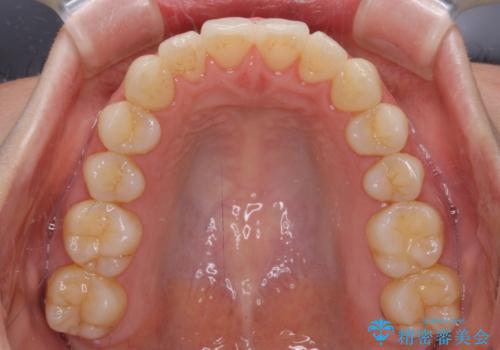

前歯の叢生とオープンバイト インビザラインでの矯正治療

- 前歯の開咬を気にして来院された患者様です。

開咬の治療は、前歯を閉じるように動かすとともに、上下臼歯を圧下(骨内にめり込ませる)させることで進めて行きます。

インビザラインは臼歯の圧下を効果的に行えるため、インビザラインを用いて矯正治療を行うこととしました。